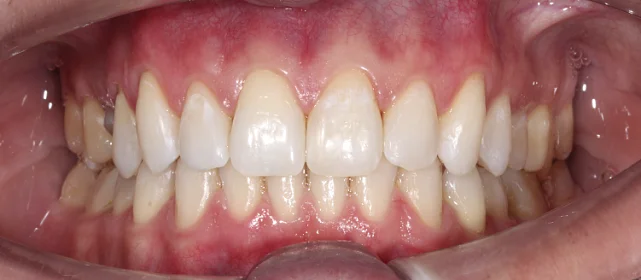

Результат

Зубы выровнены, смыкание нормализовано. Установлены несъёмные ретейнеры на обе челюсти. Пациент направлен к ортопеду.

Решение: Поставили элайнеры Invisalign на обе челюсти. Лечение заняло 4 года — случай потребовал нескольких этапов коррекции, каждый из которых последовательно приближал зубы к нужному положению. Капы менялись каждые 1–2 недели, контрольные визиты — для отслеживания прогресса и выдачи новых наборов. Зубы встали на место, смыкание пришло в норму. Зафиксировали ретейнеры на обе челюсти, пациент направлен к ортопеду для завершающего этапа.

Случай потребовал нескольких последовательных этапов коррекции. Invisalign позволяет дозаказывать капы в рамках лечения, и здесь это понадобилось — каждый следующий этап доводил положение зубов точнее. Результат достигнут, прикус стабилен, ретейнеры на месте. Пациента направила к ортопеду.